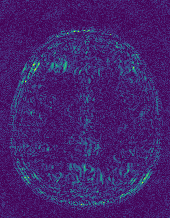

EPN is utilized to provide edge priors for later reconstruction, so the quality of the predicted edges is very important. In Fig. 10, we provide some qualitative results of the predicted edges of EPN on three multi-coil datasets. Among them, the GT edges are extracted using the Sobel operator. As can be seen from the images, our proposed EPN can predict an approximate contour for the overall subject and can reconstruct accurate edges close to the GT edges under two acceleration factors. This fully verifies the effectiveness and excellence of the proposed EPN.

(a)

(b)

(c)

(d)